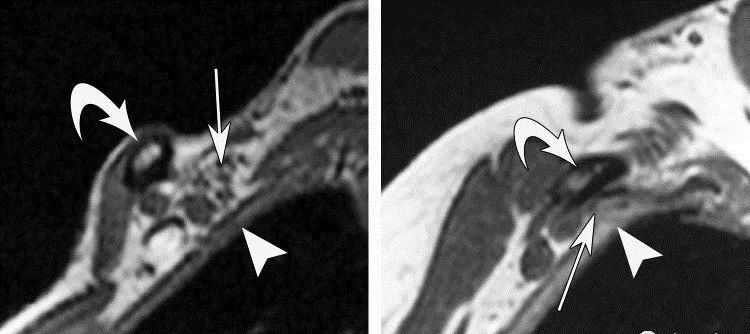

(二)病理 神经受压损伤常为假炎性肿胀样,感觉纤维最先受累,运动神经仅在晚期出现受压。此症状严重,较难恢复。神经受压时间过久则会通过交感神经导致血管舒缩障碍。锁骨下动脉血管壁可发生改变,动脉外膜增厚,间质水肿及同膜增厚伴管腔内血栓形成。早期血栓为纤维素血小板型,可出现雷诺(Raynaud)现象。 交感神经纤维收缩反射可加重指尖血管阻塞。 静脉在过度外展或内收时受到压迫,可观察到血液逆流停滞和外周静脉压上升,压迫消失后恢复正常。静脉壁反复损伤可发展类似炎症后纤维化样改变,静脉呈白色,失去半透明状态,且口径明显减小,形成侧支循环。早期发展趋势为静脉血栓,如侧支循环尚未形成,则可引起指端坏死改变。 临床表现 临床表现常见于中年妇女,20~40岁占80%,多有颈部外伤史。临床症状差异很大,且不持续 。分为神经受压和血管受压两类,神经受压的症状较为多见,也有神经和血管同时受压。 神经受压症状:有疼痛,感觉异常与麻木,常位于手指和手的尺神经分布区,也可在上肢、肩胛带和同侧肩背部疼痛并向上肢放射。晚期有感觉消失,运动无力,鱼际肌和骨间肌萎缩,4~5指伸肌麻痹形成爪形手。 臂丛神经受压:臂丛神经以跨越第1肋骨的下干最易受压,上干受压的较少,主要表现是臂丛神经下干受压的症状。 病人主要表现为:患侧肩部及上肢疼痛,无力,发病早期疼痛为间歇性,可向前臂及手部尺侧放射,肩外展及内旋时疼痛加剧。严重者可出现前臂及手部尺侧的感觉异常,甚至出现肌肉瘫痪,肌肉瘫痪及萎缩以小鱼际及骨问肌为甚,表现为爪形手畸形,有时也存在大鱼际肌及前臂肌肉肌力减退,锁骨上区有压痛并向前臂放射。 血管受压:一般病人不出现严重的血运障碍,当病变刺激血管时,可出现上肢套状感觉异常,患肢上举时感发冷,颜色苍白,桡动脉搏动减弱,锁骨下静脉严重受压时,则出现患肢远端水肿,发绀。血管严重受压时可出现锁骨下血管血栓形成,肢体远端血运障碍。 病史及症状: 既往史:大多数患者均有较长健康搜索的颈肩痛病史。 主要症状:本病的主要表现为颈肩部酸痛和不适,可向肩肘部放射患肢无力健康搜索,患者睡觉时患肢怎么放也不舒服可伴有头晕、耳鸣等症。 首诊时间:约30%的病例是在发病1年之内来诊,半数患者在1~2年来诊,另有20%患者超过2年来诊。 发病肢体:以非优势手多发,占2/3以上。 发病特点:急性发病者占55%慢性发病约占45%。 疼痛性质:均与体位关系密切,95%的患者呈间断性发作。 其他症状:几乎全部病例均有颈肩背部的异常、不适感约半数伴有疼痛。此外几乎95%的病例在睡觉时感到患肢怎么放也不舒服,同时伴有肩上举无力,少数患者可出现耳鸣、头昏及屈肘无力感。 诊断及鉴别诊断 1.诊断: 根据病史、局部体检、胸部和颈椎X线摄片和尺神经传导速度测定,一般可以明确诊断。 由于TOS患者临床表现复杂,与多种神经卡压症(如肘管)及运动神经元性疾病等症状相似,因此一种检查方法无法满足需要。 皮肤痛阈试验和两点辨别试验用于对中、晚期病人的诊断。而症状激发试验是最主要的早期诊断方法,包括“艾德森氏”试验、“过度外展”试验、“锁骨上叩击”试验、“上臂缺血”试验等。 1)“艾德森氏”征 病人端坐,双手置于膝上,将头转向患侧,下颌抬起使颈伸直,嘱病人深吸气后屏气,如桡动脉搏动减弱或消失者为阳性 2)“过度外展”试验 病人取坐位,检查者一手触摸病人桡动脉,同时将上臂被动地过度外展,如桡动脉搏动减弱或消失,腋下出现杂音者为阳性。 3)上臂缺血试验(一般认为最可靠) 即患者双上臂抬起,前臂屈曲90°,肩外展外旋,交替握拳与松开,若3min内一侧产生疼痛或不适而被迫下垂为阳性。 2.影像学 胸廓出口综合征主要依赖临床特征诊断,影像学有助于了解受压部位,解剖特征,确定手术方案:影像学检查X线颈椎片和胸片可以排除颈肋、第7颈椎横突过长、锁骨、第一肋骨畸形或其它骨性病。 平片——骨质异常 平片可以排除骨性结构的异常,图中两人都是临床证实的胸廓出口综合征的病人。 左图可以发现病人存在第七颈肋及颈七椎体横突过长; 右图则是锁骨骨折后骨痂过度形成而导致的肋骨锁骨间隙狭窄。 多普勒超声可以发现血管受压狭窄,血管造影可以确定狭窄和受压的部位: 评价动脉受压病变 静脉受压评估欠准确 臂丛显示不清 CT血管造影可用于评价动脉受压病变,图来自一个37岁的男性,图a是正常状态下的矢状位,锁骨下动脉没看到明显受压,图b是该病人手臂外展时的矢状位图,可以看到锁骨下动脉受压变窄,图cVR图直观显示血管跟周围骨骼结构的关系。值得注意的是,影像学对于静脉受压的评估相对欠准确,因为即使在正常人手臂外展时也会引起静脉受压,CT血管造影一个明显的缺点是对臂丛显示不清。 CT和MRI是一种敏感且无侵害性的方法,对TOS的确诊有一定帮助。 MRI--矢状位T1WI评价血管神经压迫最准确。 MRI可以准确观察与胸廓出口综合征相关的所有解剖结构,文献报道T1WI最有利于评估相关结构改变。这两幅图展示的是冠状位及轴位的T1WI图像。要注意的是,正常臂丛结构在所有序列上均为低信号。 相对于冠状位及轴位,矢状位对于评价血管神经压迫最准确。这是一个四十七岁的女性,左图是上臂外展前的T1WI矢状位图,臂丛没有受到明显压迫,而右图是上臂外展状态下的矢状位图,可以看到原先的结构明显受压。 电生理检查在TOS的早期无特殊价值,可能会出现F波延长,其它常常无异常发现。 晚期如尺神经运动传导速度在锁骨部减慢有较大的诊断价值。分别测定胸廓出口,肘部,前臂处尺神经传导速度。 正常胸廓出口为72m/s,肘部55m/s,前臂59m/s。胸廓出口综合征病人胸廓出口尺神经传导速度减少至32~65m/s,平均为53m/s。 3.辅助检查 上肢外展试验:上肢外展90°,135°和180°,手外旋,颈取伸展位。使锁骨下神经血管紧束压在胸小肌止点 下方和锁骨与第1肋骨间隙处,可感到颈肩部和上肢疼痛或疼痛加剧。桡动脉搏动减弱或消失,血压下降。 4.鉴别诊断 1)颈椎病 亦可出现上肢疼痛、无力、感觉异常,但颈椎病病人颈部常有压痛,压头试验及臂丛神经牵拉试验常为阳性。x线片有颈椎骨刺增生,椎间隙变窄,钩椎关节改变等退行性变的表现,CT及MRI可显示椎间盘变性及神经根、脊髓受压。 2)肘管综合征 为尺神经在肘管内受压所产生的临床综合征,表现为手无力,患肢手部尺侧感觉异常,小鱼际及骨间肌萎缩,爪形手,与本病主要累及尺神经所产生的临床表现相似,但前者无肩部症状,不波及正中神经,体征局限于肘部以下,AdSOn征、wright征、ROOs征等特殊试验阴性。 3)腕管综合征 为正中神经在腕管内受压所致,主要表现为手部桡侧2/3及桡侧3个半手指的感觉障碍,拇指对掌功能障碍,通过临床症状及检查,不难鉴别。 治疗 1.非手术治疗